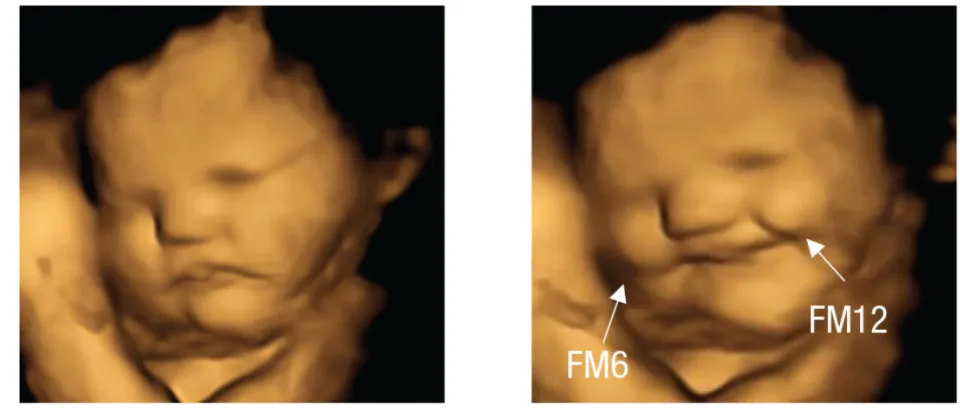

Một nghiên cứu được công bố bởi Đại học Durham cho thấy thói quen kén ăn có thể bắt đầu từ trước khi sinh. Nghiên cứu đã sử dụng công nghệ siêu âm 4D để quan sát phản ứng của thai nhi với các hương vị thực phẩm khác nhau trong bụng mẹ. Theo nghiên cứu, khi các bà mẹ tương lai ăn cà rốt, loại rau củ bổ dưỡng này, trong thai kỳ, chúng dường như kích thích "tiếng cười" hoặc nụ cười ở thai nhi đang phát triển. Tuy nhiên, khi các bà mẹ ăn cải xoăn, một loại rau lá xanh có vị đắng , thì tác dụng ngược lại xảy ra, khiến nụ cười của thai nhi chuyển thành "nét mặt cau có" hoặc "mặt chua chát".

Nghiên cứu ghi nhận bằng chứng trực tiếp đầu tiên cho thấy thai nhi phản ứng khác nhau với các mùi và vị khác nhau, một phát hiện được họ rút ra bằng cách quan sát biểu cảm khuôn mặt của thai nhi. Phân tích hình ảnh siêu âm 4D của 100 phụ nữ mang thai, các nhà nghiên cứu đã quan sát cách thai nhi phản ứng với hương vị thực phẩm mà mẹ chúng ăn.

Các bà mẹ tham gia nghiên cứu, độ tuổi từ 18 đến 40, đã được siêu âm vào tuần thứ 32 và 36 của thai kỳ. Khoảng 20 phút trước khi siêu âm, họ được cho uống một viên nang chứa khoảng 400 mg bột cà rốt hoặc cải xoăn, chất duy nhất họ tiêu thụ trong ít nhất một giờ. Hơn nữa, những người phụ nữ này không ăn hoặc uống bất cứ thứ gì khác có chứa cà rốt hoặc cải xoăn vào ngày hôm đó. Các phản ứng trên khuôn mặt cho thấy ngay cả một lượng nhỏ hương vị cà rốt hoặc cải xoăn cũng đủ để kích thích phản ứng của thai nhi.